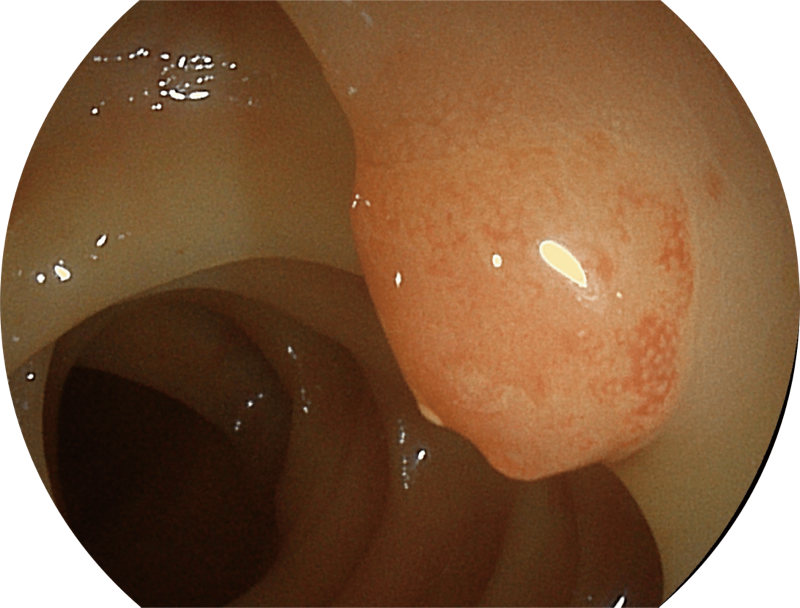

百万级像素高清传感器,1080P全高清视频信号输出,图像清晰。

能够凸显黏膜浅层和中层血管轮廓,适用于中、远景观察下的病灶识别和早癌筛查。